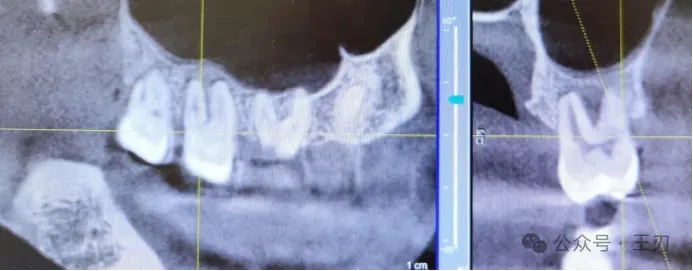

因为患者三个月前的全景片和咬合翼片都没能看出明显的骨吸收,根据探诊的结果我给她拍了CBCT:

因为CBCT是三维影像,把视图拉到靠舌侧(上图),可以发现46近中很深的牙槽骨吸收,已经到达根尖。而把视图拉到靠颊侧(下图),在同样位点46的近中就看不到明显骨吸收。这就是为什么我们不能单单凭借X光片去判断患者是否有牙周炎,探诊是最简便,无害,客观的检查手段。